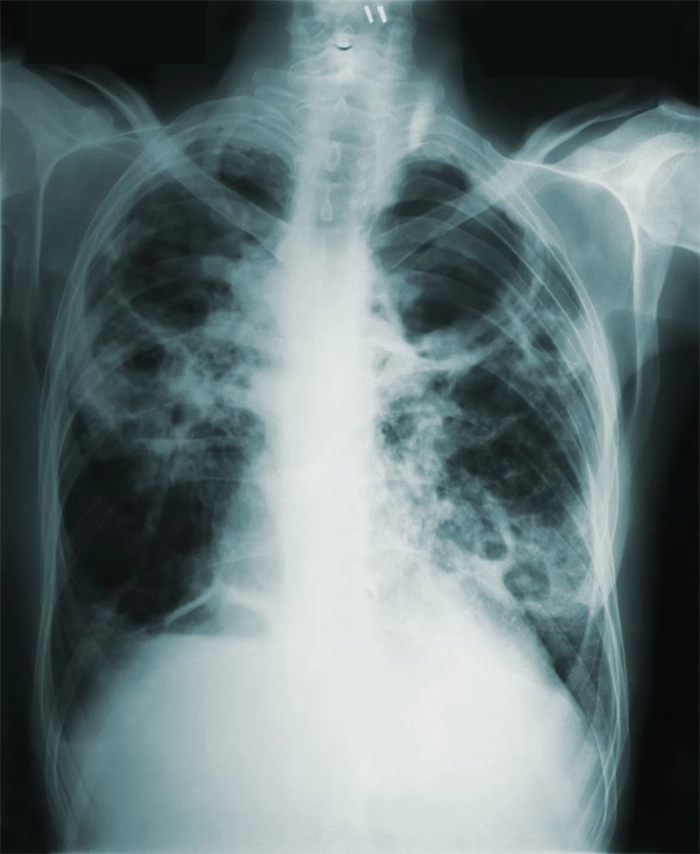

рентгенографию органов грудной клетки;

| Легкая | Осмотр, бронходилатационный тест — ежегодно. При обострении — рентген органов грудной клетки, анализ крови |

| Тяжелая | Осмотр — дважды в год, ежегодно — бронходилатационный тест и ЭКГ. При обострении — рентгенография органов грудной клетки, общий анализ крови |